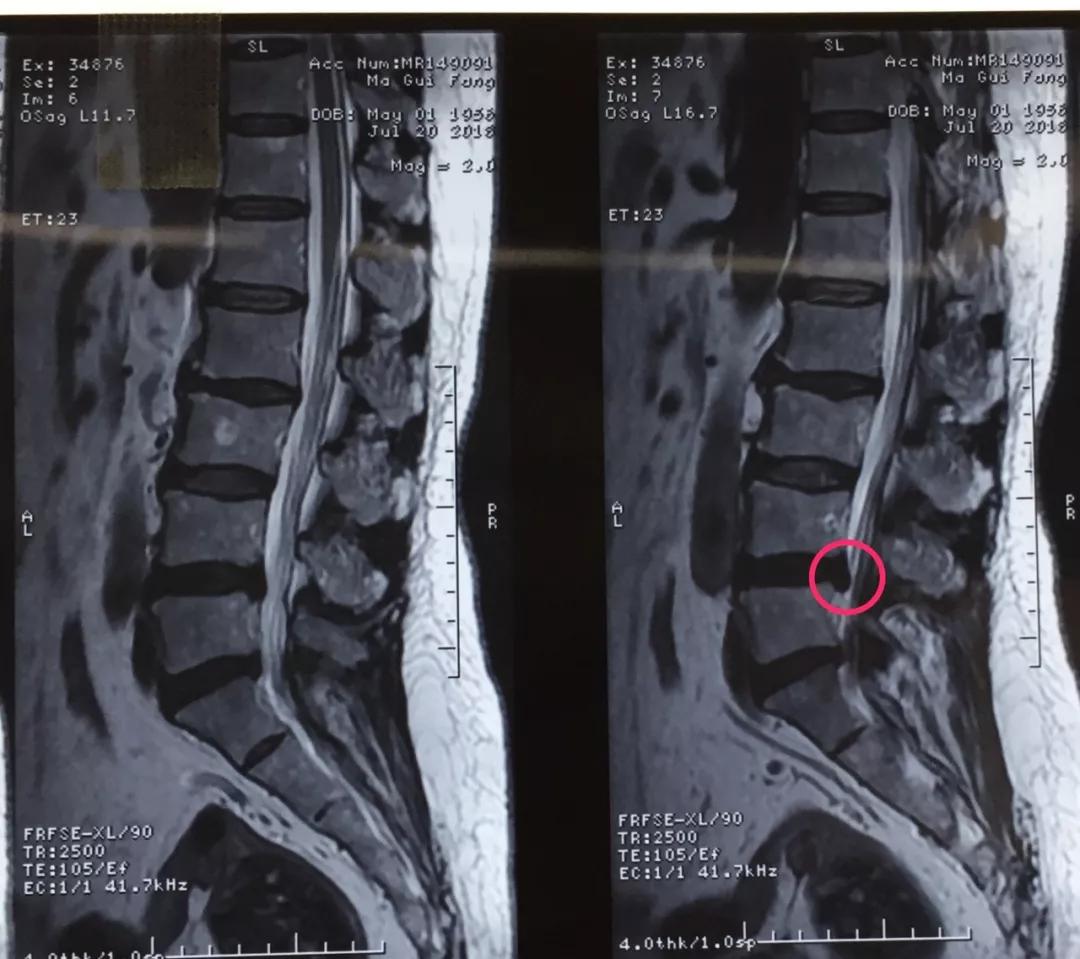

60岁的人生状态应该是退休在家,带着孙子孙女享受天伦之乐,而同样是60岁的马老太,被腰椎间盘突出症困扰了多年,稍微劳累就腰背酸痛,近几个月来又开始出现左下肢的过电样抽痛,抽的腿都抬不起来,家人带着马老太到医院做了检查说是腰椎间盘突出症,问了几家医院都说要来开刀手术,卧床两月,这下把马老太吓住了,一边是病痛折磨,一边是对手术的恐惧,正绝望之际,邻居建议马老太到西安市中心医院郭华副院长的专家门诊看一下,马老太并没有抱太大希望,那么多医院都说要手术,估计治疗方案是一样的,手术是免不了了。到中心医院后,郭华副院长仔细地询问了马老太的病史,并进行了细致的查体,然后看了看片子,对马老太说:“你这个情况确实是腰椎间盘突出症,但是不需要全麻开大刀,局麻下1cm小口把椎间盘取出来就可以了,术后就可以直接下地走路了,而且你现在检查齐全了,当天住院、当天手术、当天出院,我们叫做——椎间孔镜日间手术”,马老太半信半疑的回家考虑了几天,最终马老太还是相信中心医院的实力,24日马老太入住骨一科后,郭华副院长、严少荣主任、姬钢主任医师中午共同为马老太局麻下实施了经皮椎间孔镜下髓核摘除术,手术共计一小时,手术完马老太抬腿就不痛了,郭华副院长告诉马老太,你这个情况完全可以出院走路回家了,可把马老太高兴坏了。

郭华副院长介绍:随着人口老龄化,腰椎间盘突出症的发病数量越来越多,而医学的进步也同样日新月异,传统的开大刀手术越来越少,我院开展的经皮椎间孔镜下髓核摘除术(PELD)是近几年来成熟起来地一种微创手术方式,局麻下不到一小时就可以取出压迫神经根的椎间盘,术后即刻解除疼痛下地走路,甚至可以做到日间手术(当日住院、当日手术、当日出院),医保报销后花费少,效果立竿见影,得到了广大患者的认可和好评。希望医学德进步给广大病患带来福音,希望我院的新技术能为更多的病人解除病痛。